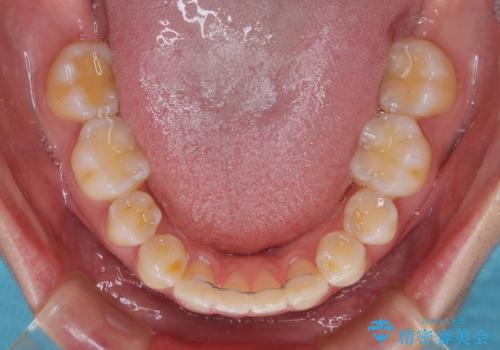

下顎前歯の欠損歯列 ワイヤー装置での矯正治療

1年弱で治療方針を変更したため、治療期間は長くなりましたが、スペースは無事に閉じ、咬合の違和感なく仕上げることができました。

ただし、両方の臼歯部は理想的な咬合とは言えないため、咬合による歯の外傷を防ぐため、就寝時にはマウスピースを継続使用するようお願いしております。